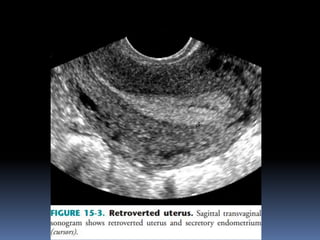

This document contains an image gallery from Dr. Mohit Goel showing various uterine anomalies and ovarian cysts. It includes images of an arcuate and unicornuate uterus, endometritis, a twisted ovarian pedicle, dermoid cysts of varying sizes and echogenicity containing hair, fat, and calcifications, and a combination dermoid cyst showing both mesh and plug structures. The gallery provides ultrasound images of different gynecological conditions for medical education and reference.